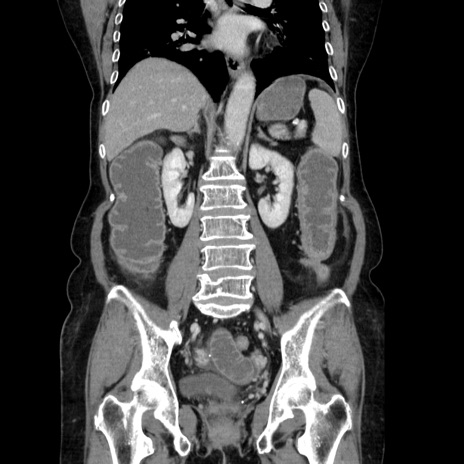

症例5(冠状断像)

【症例】70歳代女性

【主訴】お腹が張る

【現病歴】1週間くらい前から腹部膨満の自覚あり。昨日夜から増悪したため、本日救急外来受診。

【身体所見】意識清明、BT 36.5℃、BP 165/106mmHg、HR 80bpm、SpO2 98%、腹部:膨満、軟、自発痛・圧痛なし、触診にて不快感あり、腸蠕動音:減弱

【データ】WBC 12600、CRP 1.04